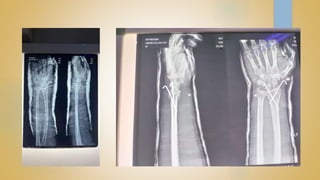

• DISTAL RADIUS FRACTURES ARE THE MOST COMMON

ORTHOPAEDIC INJURY AND GENERALLY RESULT FROM FALL ON AN

OUTSTRETCHED HAND

• DIAGNOSIS IS MADE CLINICALLY AND RADIOGRAPICALLY